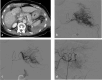

Methods: This is a retrospective study with Institutional Review Board approval. The medical records of 450 patients with BSI treated between January 2016 and December 2022 were reviewed. Seventy-two patients were treated with splenic artery embolization (SAE), met the study criteria, and were eligible for data analysis. Spleen injuries were graded in accordance with the American Association for the Surgery of Trauma Organ Injury Scale. Univariate data analysis was performed, with P < 0.05 considered statistically significant.

Results: The splenic salvage rate was 90.3% (n = 65/72). Baseline demographics were similar between the groups (P > 0.05). Distal embolization with Gelfoam® had similar rates of splenic salvage to proximal embolization with coils (90% vs. 94.1%, P > 0.05). There was no significant difference in the rate of splenic infarction between distal embolization with Gelfoam® (20%, 4/20) and proximal embolization with coils (17.6%, 3/17) (P > 0.05). There was no significant difference in procedure length (68 vs. 75.8 min) or splenic salvage rate (88.5% vs. 92.1%) between proximal and distal embolization (P > 0.05). There was no significant difference in procedure length (69.1 vs. 73.6 min) or splenic salvage rate (93.1% vs. 86.4%) between Gelfoam® and coil embolization (P > 0.05). Combined proximal and distal embolization was associated with a higher rate of splenic abscess formation (25%, 2/8) when compared with proximal (0%, 0/26) or distal (0%, 0/38) embolization alone (P = 0.0003). The rate of asymptomatic and symptomatic splenic infarction was significantly higher in patients embolized at combined proximal and distal locations (P = 0.04, P = 0.01).

Conclusion: The endovascular management of BSI is safe and effective. The overall splenic salvage rate was 90.3%. Distal embolization with Gelfoam® was not associated with higher rates of splenic infarction when compared with proximal embolization with coils. Combined proximal and distal embolization was associated with a higher incidence of splenic infarction and splenic abscess formation.